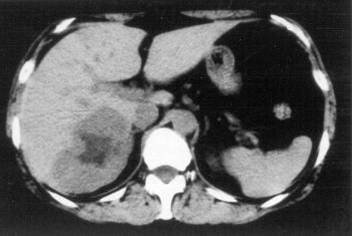

Liver abscess can develop either following the severe inflammation of the biliary ducts and the gallbladder or following a tumorous necrosis or by the spread of an external inflammation to the liver. By the help of the US, a cystic lesion can be seen with multiple internal echos containing gas bubble frequently as well. In order to determinate the further therapy, contrast enhanced CT examination can be needed, if the US imaging of the entire liver was not possible. An avascular intrahepatic lesion can be seen well on the CT with a contrast enhancing wall (sometimes multifocal as well) (Figure 30). An US or CT guided percutaneous drainage can provide a therapeutic result depending on the lesion's size and location (Figure 31).

Figure 30: Abscess in the liver, native CT